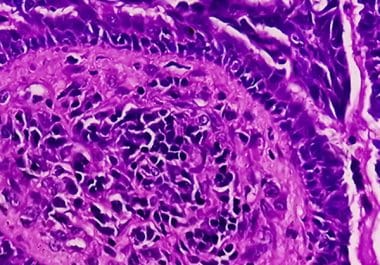

Lorazepam used to relieve stress may cause inflammation that promotes tumor growth and shortens progression-free survival, study says. A medication commonly used to ease the stress caused by cancer diagnosis and treatment may be...